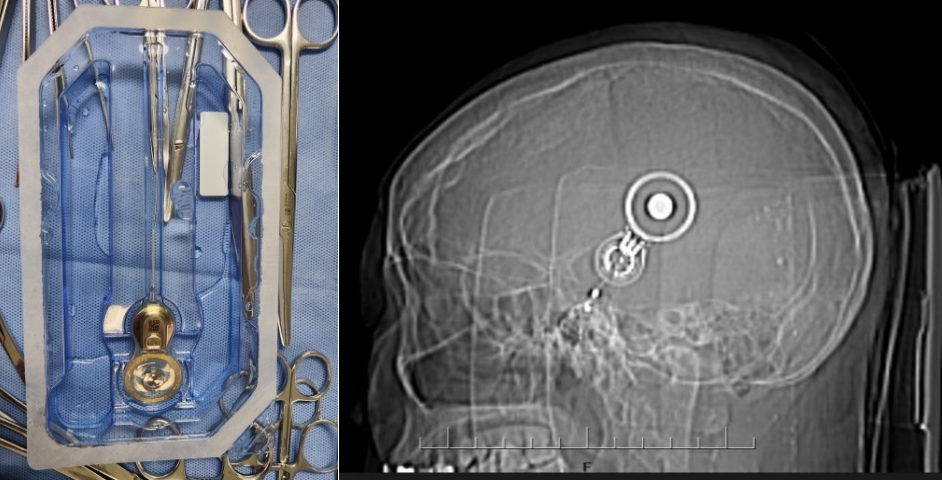

入院后,财神捕鱼 耳鼻咽喉科专家团队对徐某进行了全面细致的检查和评估,结合他的具体情况,制定了个性化的手术方案。手术过程顺利,成功将集采的人工耳蜗植入徐某耳内,术中神经电生理监测,耳蜗电极均正常工作,术后耳蜗CT显示电极位置正确。术后,经过医护人员精心护理和康复指导,徐某恢复良好,各项指标正常,顺利出院。主刀医生白忠主任叮嘱患者,1个月后返院,人工耳蜗开机后,患者就可以听到声音了,恢复有声世界。

据财神捕鱼 耳鼻咽喉科专家白忠主任医师介绍,人工耳蜗是一种电子装置,通过植入体内的电极系统直接刺激听神经,帮助重度、极重度感音神经性耳聋患者恢复听力。以往,人工耳蜗价格高昂,让许多患者望而却步。此次国家集采政策落地云南后,人工耳蜗价格大幅下降,极大减轻了患者的经济负担,让更多听障患者有机会接受治疗,重获听力。